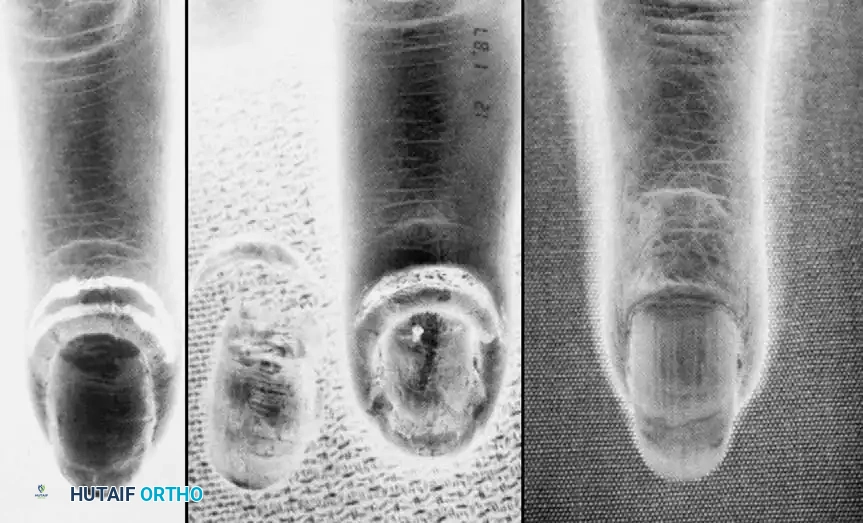

Differential Diagnosis: Herpetic Whitlow

Before proceeding with any surgical intervention, the surgeon must definitively rule out Herpetic Whitlow, an infection caused by Herpes Simplex Virus (HSV) type 1 or 2.

Herpetic whitlow is an occupational hazard frequently seen in healthcare workers (dental hygienists, respiratory therapists) and immunocompromised patients. It presents as a localized area of swelling characterized by the eruption of clear, coalescing vesicles on an erythematous base. Unlike bacterial paronychia, the fluid within these vesicles is initially clear, though it may become cloudy later. Lymphangitis and epitrochlear or axillary lymphadenopathy are commonly associated.

Diagnostic Confirmation:

* Tzanck Smear: Reveals multinucleated giant cells.

* Viral Culture/PCR: Confirms HSV DNA from vesicular fluid.

* Serum Antibody Titers: Useful for establishing primary vs. recurrent infection.

🛑 Pitfall: Incising a Herpetic Whitlow

Herpetic whitlow is a strictly self-limiting condition, typically resolving over 3 to 4 weeks. Surgical incision and drainage is absolutely contraindicated. Incising a herpetic lesion does not relieve pain; rather, it risks secondary bacterial superinfection, delayed healing, and potential systemic dissemination of the virus. Management consists of dry dressings, oral antivirals (e.g., acyclovir or valacyclovir) if initiated early, and observation.